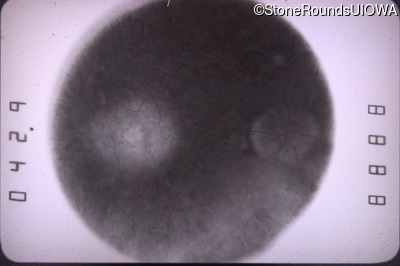

Fundus Photography - Right - 20/80 +2

Exemplar